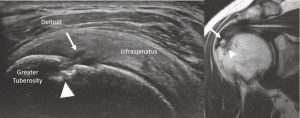

The supraspinatus tendon’s normal appearance has a curved contour deep to the deltoid, and the greater tuberosity has a notch at the insertion. It is at this notch that it is common to see anisotropy, which should not be confused with a tear (Figure 7).

Full-thickness tearing is seen with fiber disruption, fluid collection and tendon retraction similar to full-thickness tearing in the Achilles (or any) tendon (Figure 8). The anatomy can be compared to MRI.